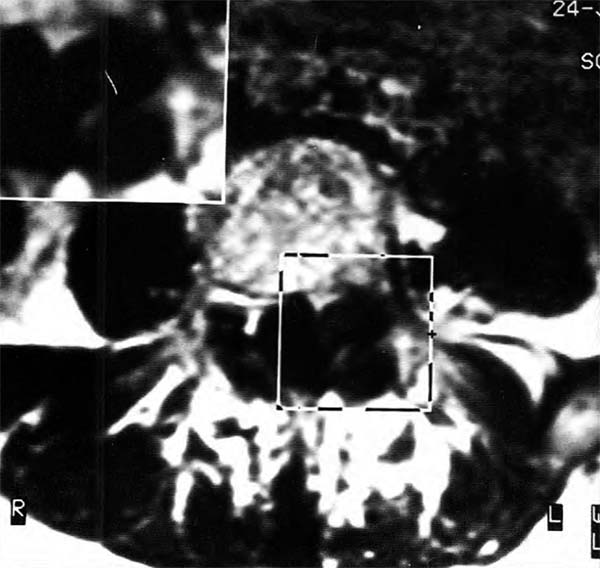

Paciente varón de 70 años con lumbociatalgia izquierda de 8 meses de evolución y parestesias en pie izquierdo, con hiporreflexia aquilea bilateral y Lasegue a 30º en miembro inferior izquierdo. La TAC demostró una masa yuxtaarticular L4-L5 izquierda de bordes calcificados y centro hipodenso (Fig. 1A). La IRM demostró una masa hipointensa en Ti con borde levemente hipointenso en T2 en contacto con la articulación (Fig. 1B). Se extirpó la lesión totalmente por vía posterior unilateral con desaparición de los síntomas. La histopatología demostró que la lesión era un QS.

Fig 1. Caso 1